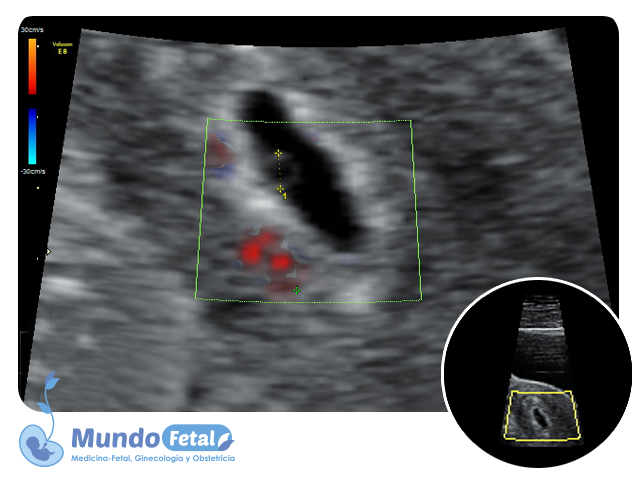

Ultrasonido Temprano 1er Trimestre (Menor 11 Semanas)

Estudio que nos permite la confirmación del embarazo, numero de bebes, valoración de líquido amniótico, placenta, vitalidad por medio de la frecuencia cardiaca, crecimiento armónico y edad gestacional estimada, descartando alguna complicación propia de esta edad.